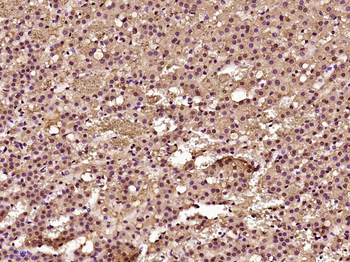

Phospho-Smad3 (Ser423 + Ser425) Rabbit Polyclonal Antibody [orb6983]

FC, IF, IHC-Fr, IHC-P, WB

Bovine, Canine, Equine, Gallus

Human, Mouse, Porcine, Rat

Rabbit

Polyclonal

Unconjugated

100 μl, 200 μl, 50 μlPhospho-SMAD5 (Ser463 + Ser465) Recombinant Rabbit Monoclonal Antibody [orb559123]